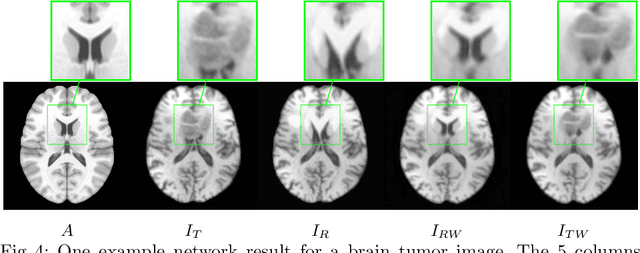

Abstract:Registration of images with pathologies is challenging due to tissue appearance changes and missing correspondences caused by the pathologies. Moreover, mass effects as observed for brain tumors may displace tissue, creating larger deformations over time than what is observed in a healthy brain. Deep learning models have successfully been applied to image registration to offer dramatic speed up and to use surrogate information (e.g., segmentations) during training. However, existing approaches focus on learning registration models using images from healthy patients. They are therefore not designed for the registration of images with strong pathologies for example in the context of brain tumors, and traumatic brain injuries. In this work, we explore a deep learning approach to register images with brain tumors to an atlas. Our model learns an appearance mapping from images with tumors to the atlas, while simultaneously predicting the transformation to atlas space. Using separate decoders, the network disentangles the tumor mass effect from the reconstruction of quasi-normal images. Results on both synthetic and real brain tumor scans show that our approach outperforms cost function masking for registration to the atlas and that reconstructed quasi-normal images can be used for better longitudinal registrations.